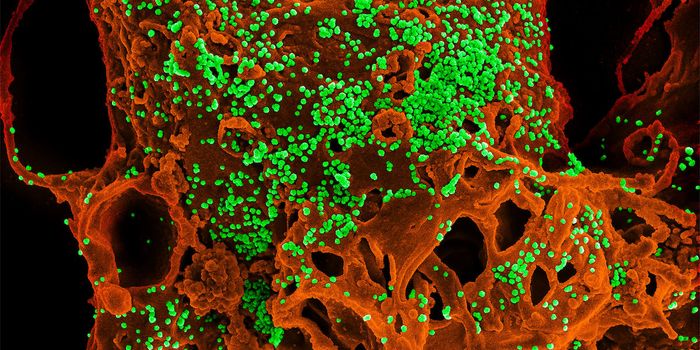

SEP 08, 2024MicrobiologySARS-CoV-2, the pandemic virus that causes COVID-19, has mutated endlessly since it burst on the scene in late 2019. An ...

AUG 27, 2024MicrobiologySince the start of the COVID-19 pandemic, the virus that causes the illness - SARS-CoV-2 - has had a practically infinit ...